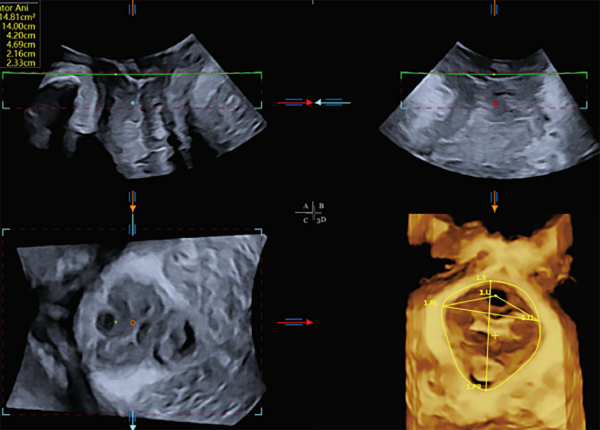

- VNAVLN - Otra innovación desarrollada por VINNO es "VNavln". Esta herramienta muestra imágenes, navegando dentro del volumen 3D, como un endoscopio virtual.

La vesícula biliar con la herramienta VNavIn 3D muestra la vista panorámica en tres dimensiones de la vesícula biliar interna. Esto ayuda a visualizar una lesión / estructura y su anatomía circundante.

VINNO Technology introduce una nueva tecnología que utiliza inteligencia artificial (IA) para la medición pélvica, VAim Levator Ani y VAim Ant. Pelvic, ésta proporciona resultados de medición pélvica con un solo toque. Permite evaluar la estructura pélvica posparto de una manera fácil y precisa.

Los ecógrafos VINNO cuentan con esta tecnología, esto le proporcionará una ventaja estratégica a su clínica u hospital.

Realizará estudios, que normalmente requieren mucho tiempo, en un instante.